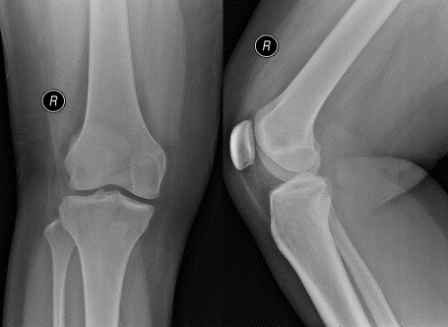

On examination, she was walking with an antalgic gait. Knee effusion was clinically detected. No focal bony tenderness. Knee range of motion was slightly restricted. The knee was grossly stable. Radiograph of right knee was performed.

Q. What are your thoughts on the findings of the knee radiograph?

Normal bony contour. No fracture noted. Raised suprapatellar fat pad suggesting intra-articular knee effusion.

Radiographs likely show non-specific features such as joint effusion and bone erosions. CT and ultrasound can also demonstrate the hypertrophic synovium as a slightly hyperdense/echogenic soft tissue mass. Bony erosion can be seen well on CT scan [4].